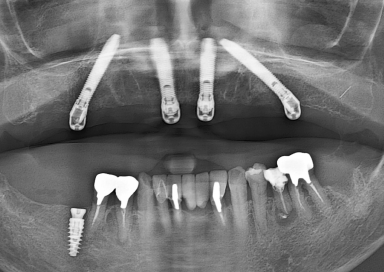

All-on-4(オールオンフォー)は、上顎・下顎に4本ずつのインプラントを埋入し、

その上に全ての人工歯を固定する画期的な治療法です。

従来のように10本以上のインプラントを必要とせず、

骨のある部分を活かして傾斜埋入することで、骨移植なしでも対応できるケースが多いのが特徴です。